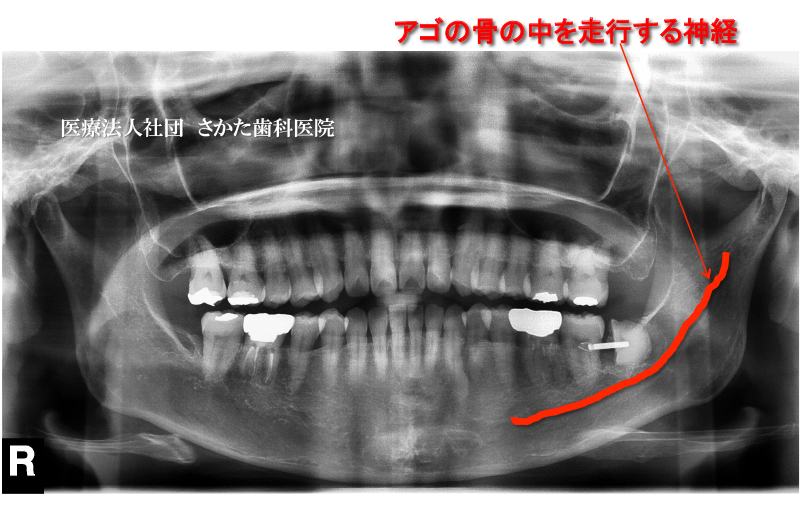

当院では「親知らず」の抜歯においてCT装置によるエックス線画像診断を行いベストな術式の選択を行っております。

以下は「親知らず」の抜歯において神経損傷のリスクを回避する処置を行い安全・安心な抜歯を行った症例です。

- 初診時 エックス線写真

※下あごの「親知らず」が血管・神経と重なる場合抜歯による神経損傷は3~5%の確率で発生すると言われています。